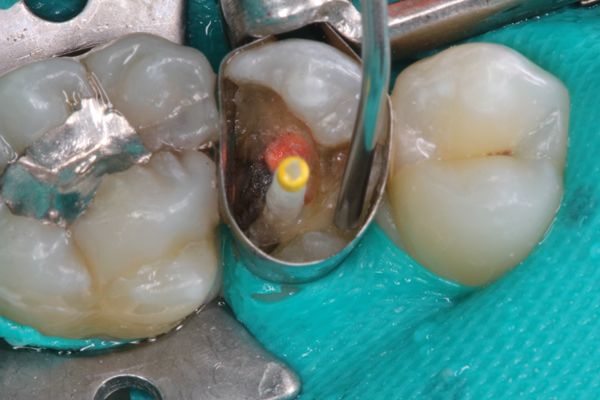

(2.) Preparation of tooth No. 31.

Figure 2

Higher viscosity bulk-fill composites can be used up to the occlusal surface, however. Two clinical cases using the bulk-fill composites Tetric EvoCeram Bulk Fill and SonicFill are presented in Figure 2 through Figure 6. Limitations when placing a high-viscosity bulk-fill composite include difficulty of condensing and esthetic restraints. Condensing a high-viscosity resin composite ensures adequate adaptation to the tooth preparation and sufficient interproximal contacts. Condensing 4 mm of composite is more difficult than condensing 2 mm. To ensure adequate interproximal contacts, a sectional or circumferential matrix with an inciso-gingival curvature can be used to obtain a tight area of contact gingival to the marginal ridge. A ring should be used to help separate the teeth and improve the tightness of the contact area.